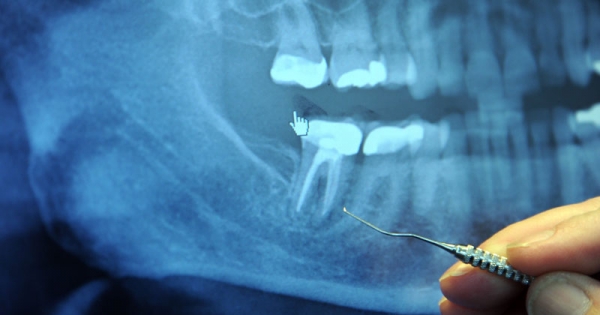

看牙医想必是不少人心中的一件苦差事,儘管我们日常努力保养牙齿,还是无法保证能100%逃过蛀牙的命运。事实上,传统的补牙约有10-15%的失败率,补牙失败就得进行根管治疗;不过近期英…